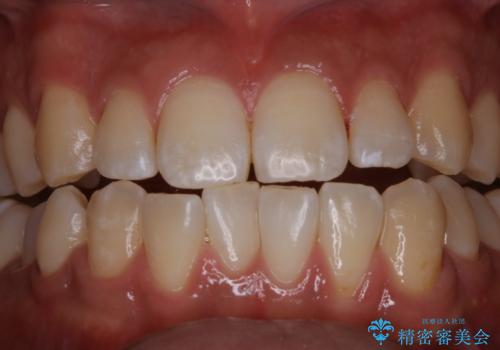

コーヒーの着色が前歯について目立つ

- コーヒーを毎日飲むので、どうしても着色がついてしまう。前歯の目立つ着色をきれいにとってほしいとのことでした。

PMTC60分コースを行いました。